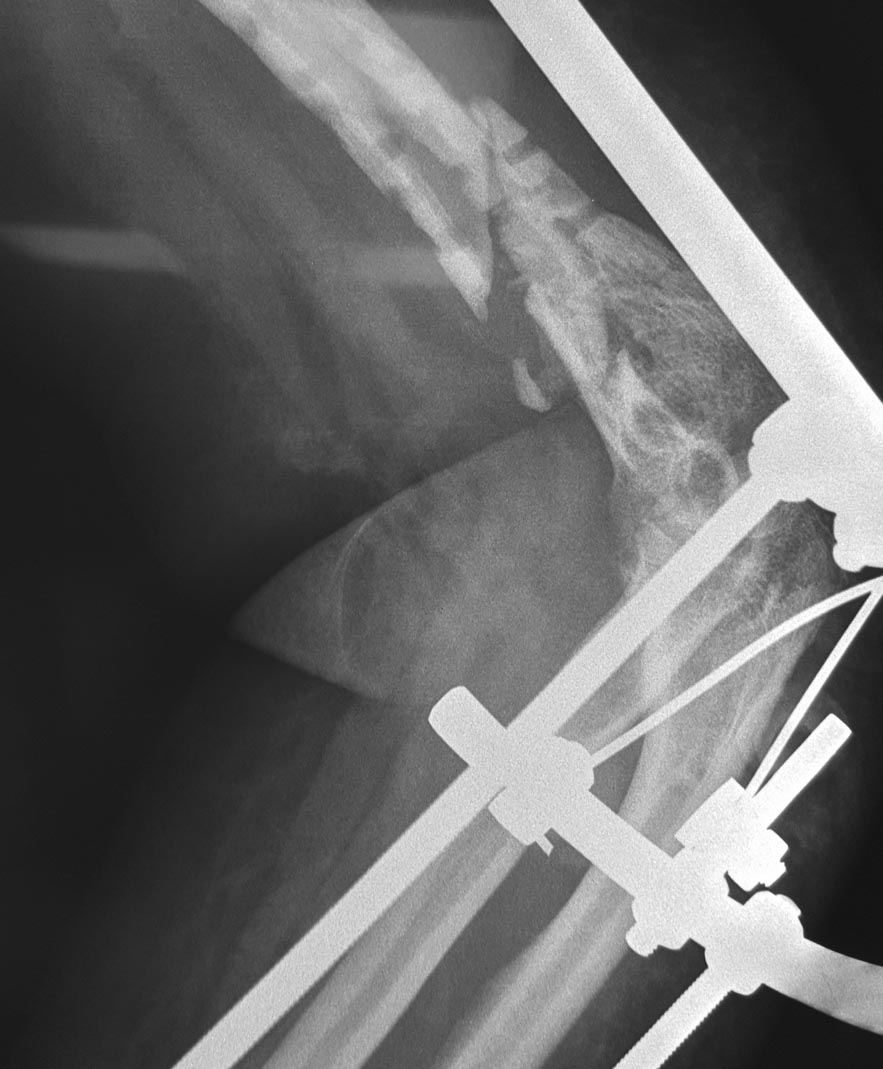

Уважаемые коллеги! Помогите с тактикой дальнейшего лечения пациентки Д

56 лет: февраль 2015 закрытый многооскольчатый перелом левого плеча в

дистальной трети, остеосинтез пластиной с ОК - через 2 недели вырваны

дистальные винты, повторный остеосинтез пластиной с угловой

стабильностью через 1 месяц вырваны винты, угроза инфицирования

гематомы, удаление пластины, спице стержневой АВФ. заживление первичное,

последний месяц без свищей и отделяемого.